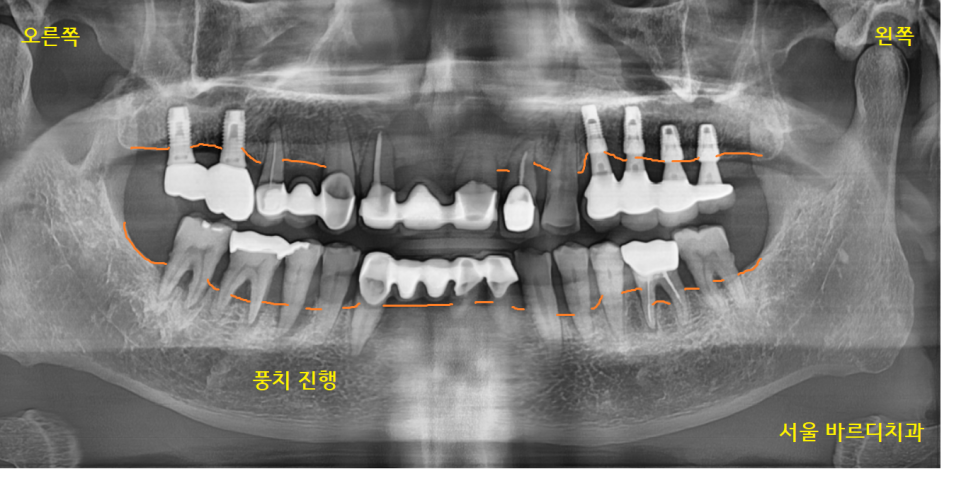

전반적으로 풍치가 진행된 상황이었습니다.

잇몸뼈가 많이 내려간 상황

23.04.24